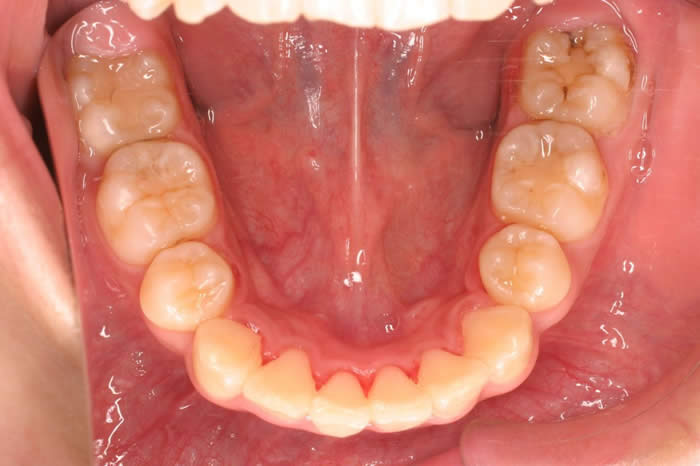

初診時下顎

初診時の口腔内写真です。重度の上顎前突症と叢生の合併症です。下顎をみると左側の第一小臼歯と右側側切歯が完全に歯列から逸脱し、上顎の前歯は下顎の前歯より1cm以上前突しています。

上顎両側の第一小臼歯と下顎両側の第一小臼歯を抜歯(合計4本)し、さらに、効果的に上顎前歯の後退をはかるため上顎口蓋側臼歯部に固定源のための歯科矯正用アンカースクリューを植立することにしました。